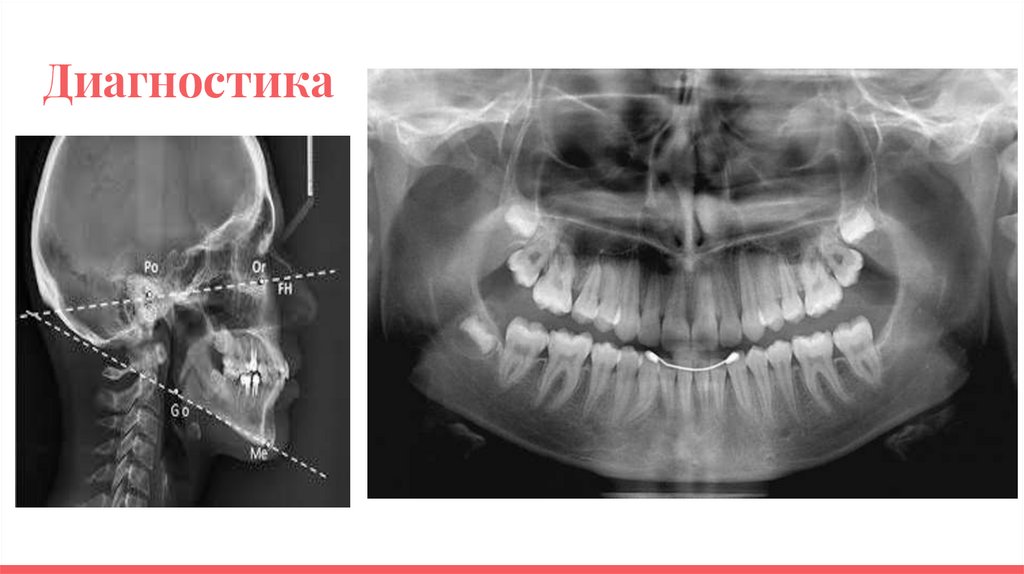

Диагностика